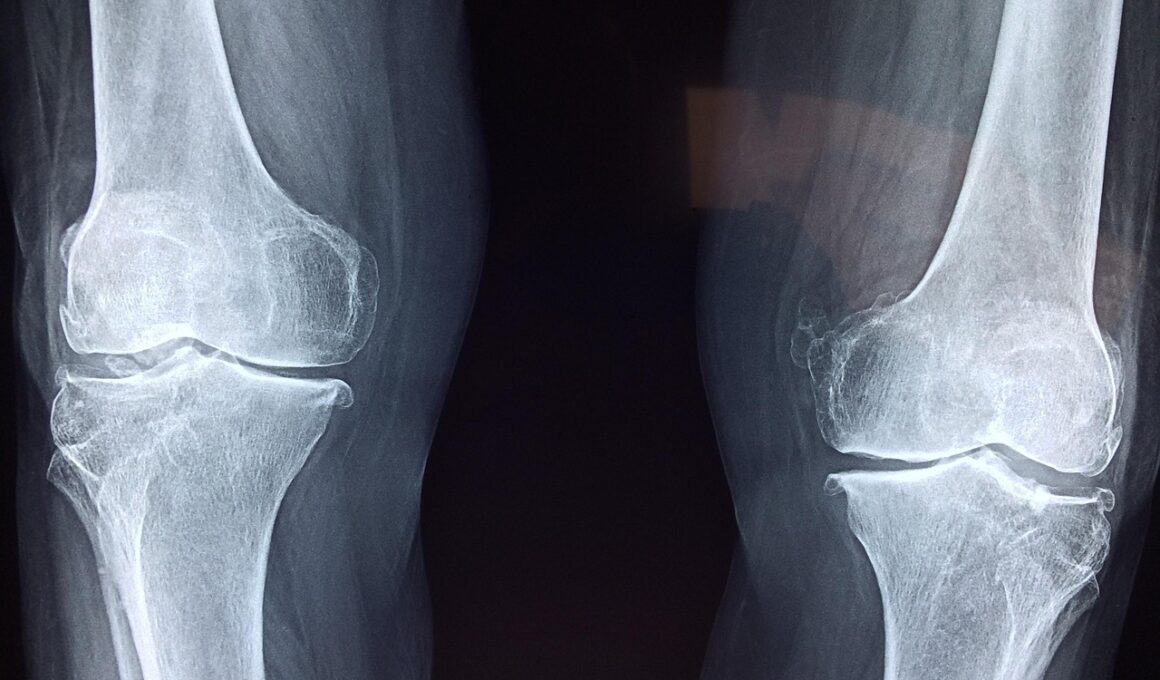

Several risk factors contribute to knee injuries, and recognizing them can guide preventive strategies. Age plays a significant role, as older individuals often face increased risks due to age-related wear and tear. Similarly, individuals with a previous history of knee injuries are at a higher risk of recurring issues. Furthermore, biological factors such as gender can influence risk; studies show that women are more prone to certain types of knee injuries compared to men. Another significant factor to consider is body weight. Excess body weight puts additional stress on the knee joints, raising the probability of injuries during activities. Additionally, overuse can lead to chronic conditions and acute injuries. Overtraining without appropriate rest disrupts the normal recovery process, making muscles fatigued and vulnerable. Training on different surfaces can also affect injury risk. Hard surfaces may increase the impact on knees during high-impact exercises, while uneven terrains can lead to falls and awkward landings. Another critical element is the choice of activities. High-impact exercises or sudden changes in intensity can stress the knees if not approached with caution. Understanding these risk factors allows individuals to tailor their fitness approach responsibly.